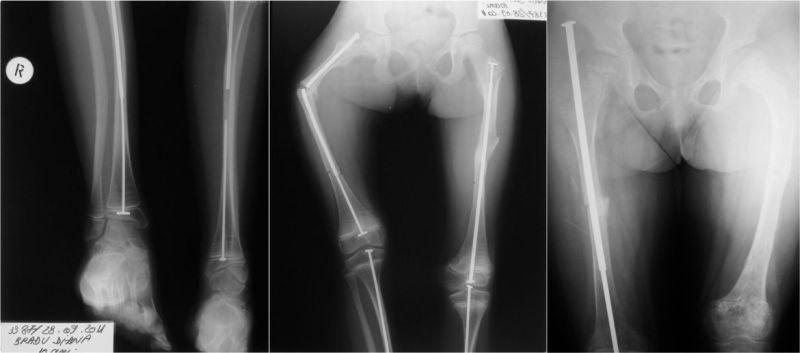

In the above-mentioned period, from the OI patients who are in the evidence of our clinic, 32 were operated on, totaling 81 surgeries. Out of these, 28 patients, aged 2-27 years, have benefited from reconstructive surgery of the pelvic limbs. Sofield-Millar osteotomies were practiced and 69 Sheffield telescopic rods were implanted in 25 patients and 43 surgeries. The coxa vara / valga correction using the Sheffield rod was applied in 6 patients and 8 hips, respectively. Circular or monoplane external fixators were used in 7 patients for the correction of deformities, lengthening and arthrodiastasis. 9 patients have benefited from various forms of bone transplant: pedicled grafts, auto- and/or allografts. An original bone reconstruction procedure is currently being studied and will be useful in the treatment of large bone defects and the thickening of the gracile diaphyses, which consists in practice of a massive contribution of free bone grafts, auto- and/or allogenic, bone substitutes and, in selected cases, periosteal substitutes, in a composite stratified construction. Postoperatively, 15 patients are able to walk while being supported by crutches or walking frames, 5 patients walk independently and 8 are still wheelchair-bound. It is important to mention that 8 children who were preoperatively dependant on the wheelchair are now walking!

在上述期间,在我们诊所登记的OI患者中,有32人接受了手术,共计81次手术。其中,28名年龄在2至27岁的患者接受了骨盆四肢的重建手术。实施了索菲尔德 - 米勒截骨术,并在25名患者的43次手术中植入了69根谢菲尔德伸缩杆。分别对6名患者的8个髋关节应用谢菲尔德杆进行了髋内翻/髋外翻矫正。7名患者使用环形或单平面外固定器进行畸形矫正、肢体延长和关节扩张。9名患者接受了各种形式的骨移植:带蒂移植、自体和/或异体移植。目前正在研究一种原始的骨重建程序,该程序将有助于治疗大的骨缺损和纤细骨干的增厚,其实际操作是大量使用游离骨移植、自体和/或异体骨替代物,以及在特定情况下使用骨膜替代物,进行复合分层构建。术后,15名患者能够借助拐杖或助行架行走,5名患者能够独立行走,8名患者仍需依赖轮椅。需要提及的是,8名术前依赖轮椅的儿童现在能够行走了!